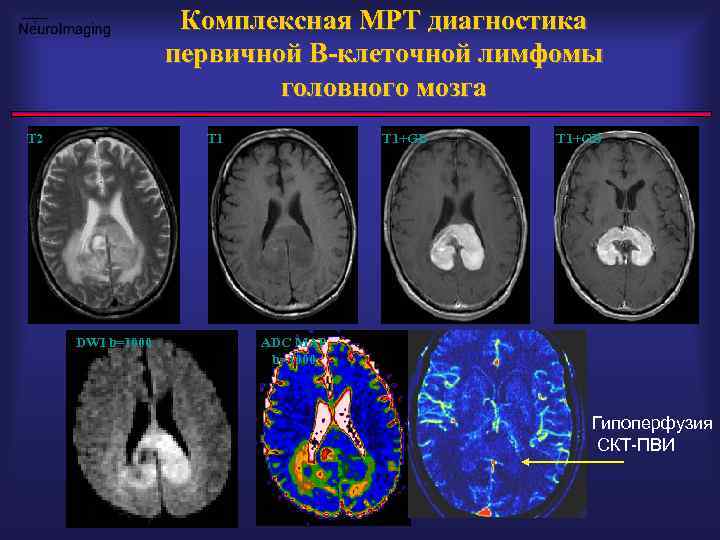

Комплексная МРТ диагностика первичной B-клеточной лимфомы головного мозга T 2 T 1 DWI b=1000 T 1+GD ADC MAP b=1000 Гипоперфузия СКТ-ПВИ